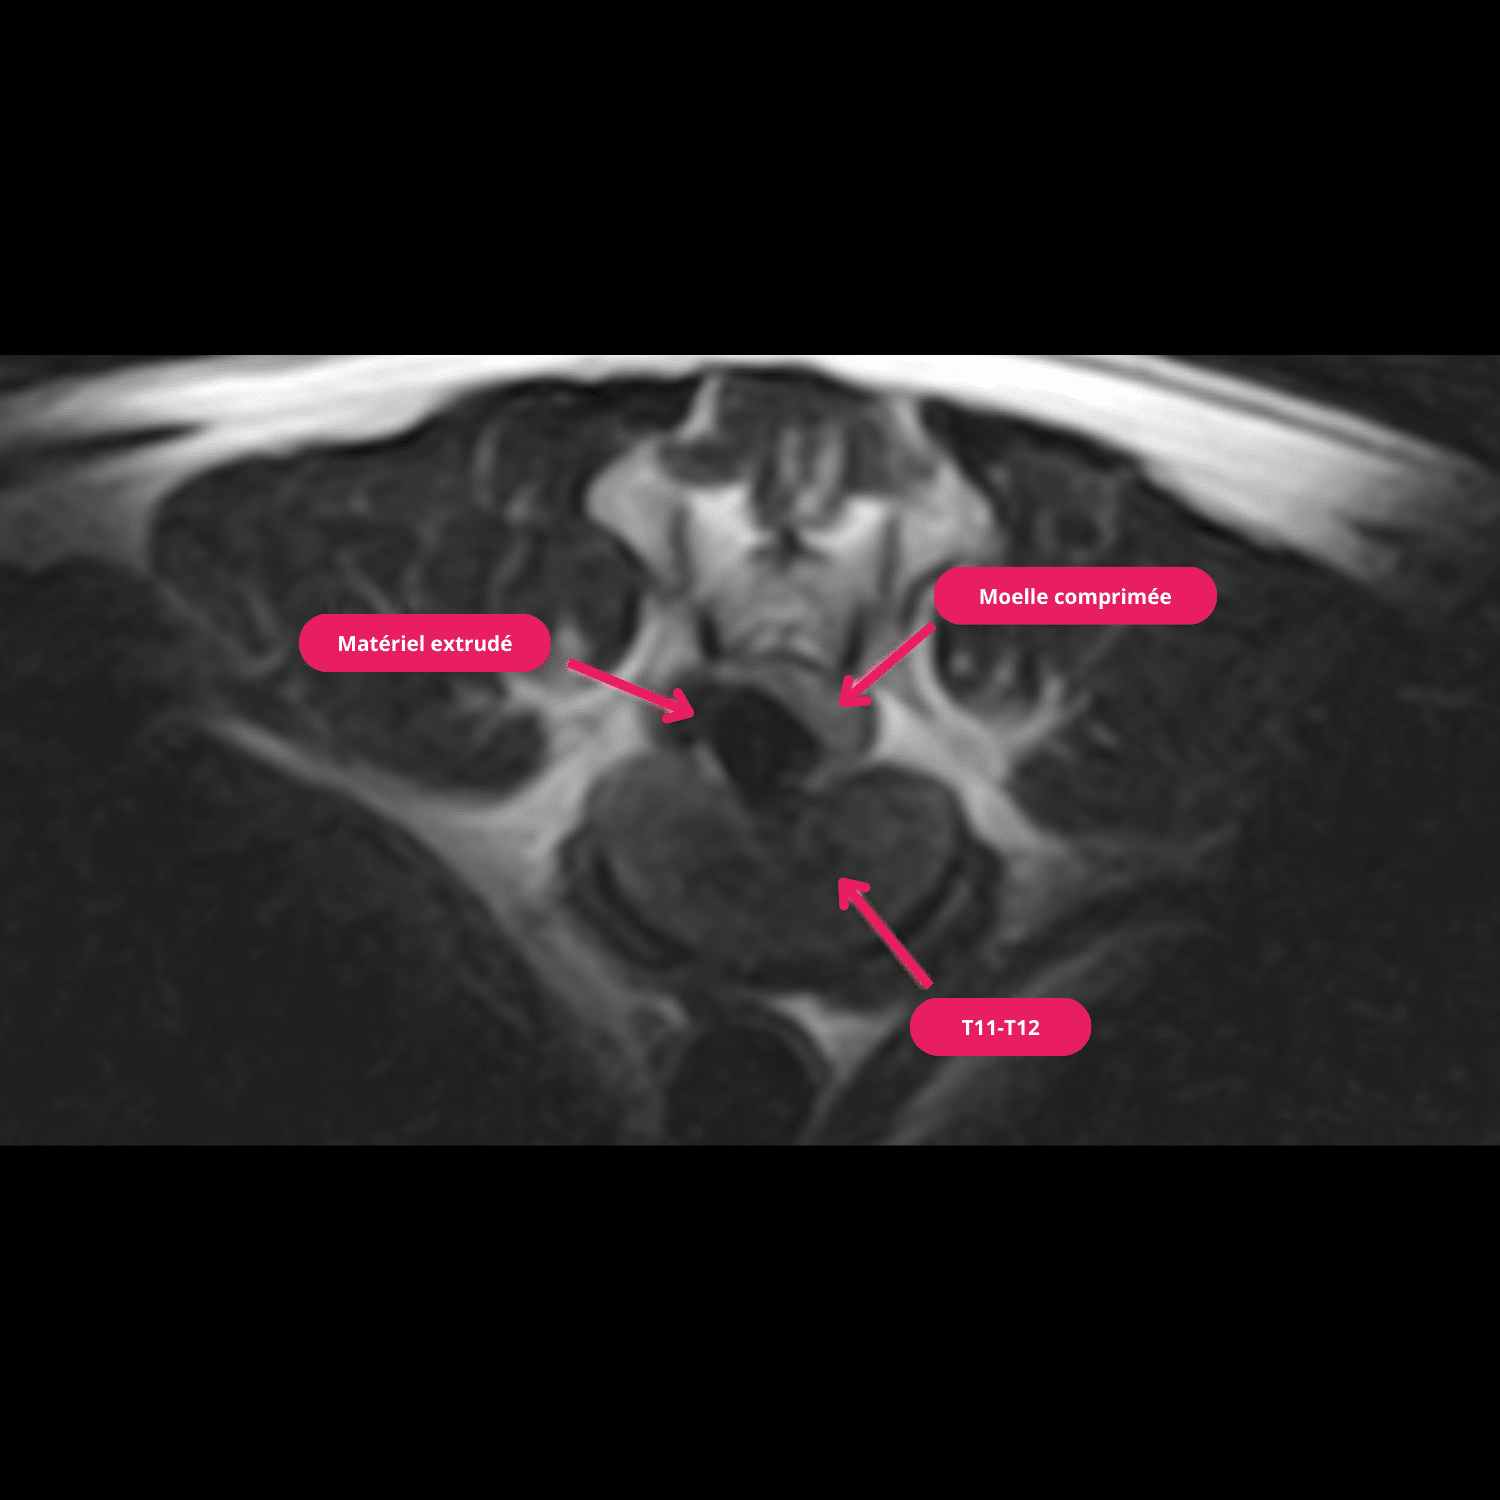

Une nouvelle IRM de la colonne montre une compression médullaire focale, extradurale latérale droite sévère avec une portion foraminale en regard du disque T11-T12 par du matériel minéralisé. L’ancien site d’hémi-laminectomie est visible en L2-L3 à droite et ne montre aucune anomalie, ni aucune récidive tumorale.

Cette lésion est compatible en priorité avec une hernie discale ; une prise en charge chirurgicale est retenue par le propriétaire étant donné le bon pronostic pour cette lésion et l’absence de récidive.

Une hémi-laminectomie droite en T11-T12 est réalisée et permet de retirer une importante hernie discale subaiguë. Après 3 jours de soins post opératoires au sein de l’hôpital, le chien rentre à la maison ambulatoire. Un contrôle postopératoire à un mois confirme une normalisation ambulatoire et nerveuse du chien.